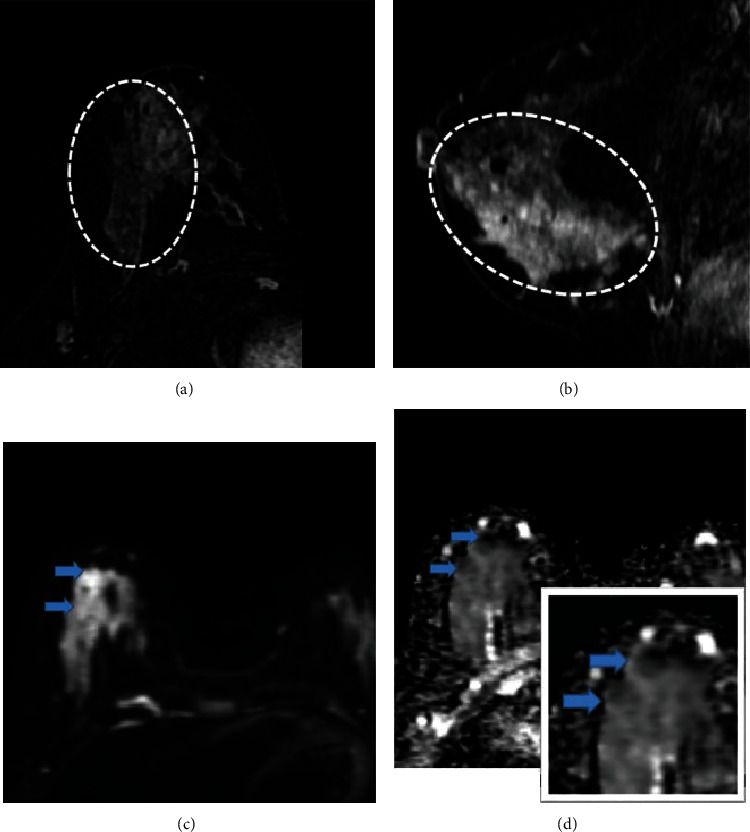

Dynamic contrast-enhanced magnetic resonance imaging (DCE-MRI) is a highly sensitive breast imaging modality in detecting breast carcinoma. Nonmass enhancement (NME) is uniquely seen on MRI of the breast. The correlation between NME features and pathologic results has not been extensively explored. Our goal was to evaluate the characteristics of probably benign and suspicious NME lesions in MRI and determine which features are more associated with malignancy. We performed a retrospective research after approval by the hospital ethics committee on women who underwent breast MRI from March 2017 to March 2020 and identified 63 lesions of all 400 NME that were categorized as probably benign or suspicious according to the BI-RADS classification (version 2013). MRI features of NME findings including the location, size, distribution and enhancement pattern, kinetic curve, diffusion restriction, and also pathology result or 6-12-month follow-up MRI were evaluated and analyzed in each group (probably benign or suspicious NME). Vacuum-guided biopsies (VAB) were performed under mammographic or sonographic guidance and confirmed with MRI by visualization of the inserted clips. Segmental distribution and clustered ring internal enhancement were significantly associated with malignancy (p value<0.05), while linear distribution or homogeneous enhancement patterns were associated with benignity (p value <0.05). Additionally, the plateau and washout types in the dynamic curve were only seen in malignant lesions (p value <0.05). The presence of DWI restriction in NME lesions was also found to be a statistically important factor. Understanding the imaging findings of malignant NME is helpful to determine when biopsy is indicated. The correlation between NME features and pathologic results is critical in making appropriate management.

Abstract Image